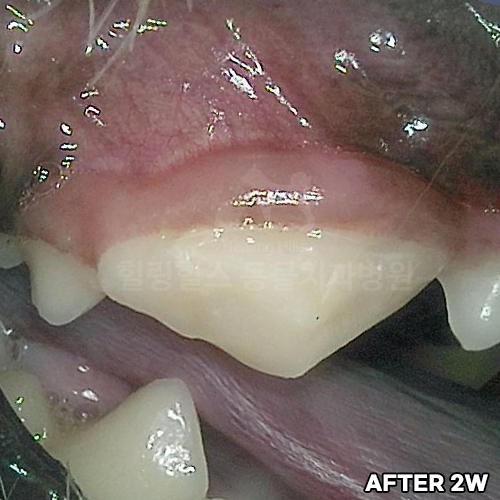

턱뼈 부러뜨리는 강아지치근단농양! 2.3kg 초소형견 발치하지 않고 신경치료하여 자기치아 살리는 힐링힐스